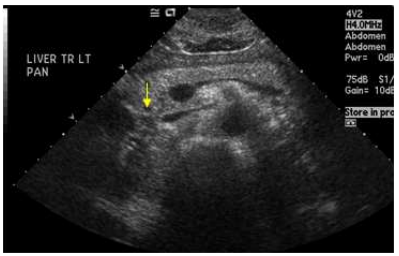

65.40歲女性發現乳房腫塊,乳房超音波檢查呈現病灶如下圖,最有可能的診斷為下列何者?

(A)乳房膿瘍 (B)惡性腫瘤 (C)囊腫 (D)良性纖維腺瘤